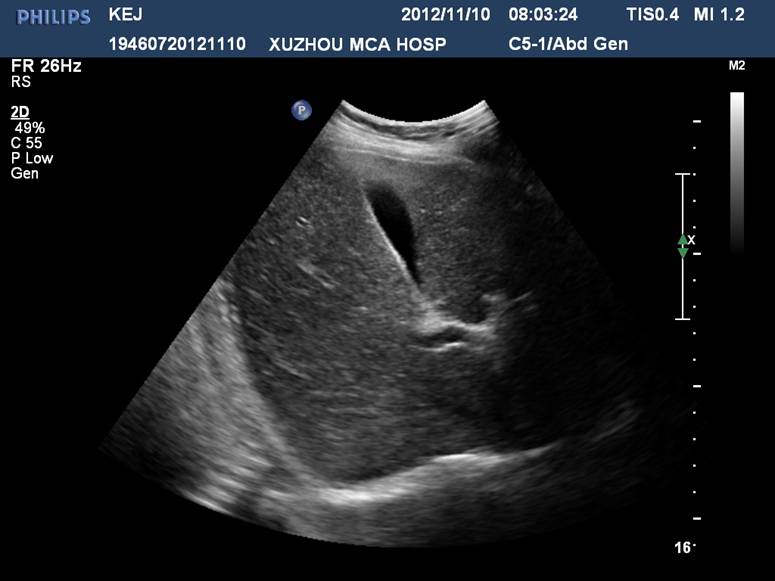

门静脉从第一肝门开始,分左右两大支。左支沿横沟向左侧横行行走,名左支横段,待抵达左内、外叶交界处,折向足端走,与横段垂直,形成独特的“C”形结构称矢状段, 末端稍膨大称囊部,与肝圆韧带相连,后者为脐静脉闭锁后的残迹。

门静脉左干横部、矢状部及左内叶支和左外叶上、下段支的空间投影图像呈“工”字形:

肝左内外叶的超声分界(肝圆韧带-门静脉左支矢状部-静脉韧带)